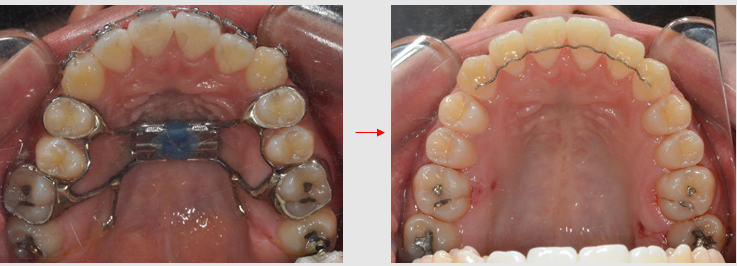

MARPE를 이용한 비발치 교정의 과정 3

좁은 상악을 넓혀주면 치열 형태가 뾰족한 'V' 모양에서 'U' 형태로 둥글어집니다.

좁고 뾰족하던 치열이 둥글게 되면서 가지런하게 배열되었습니다.